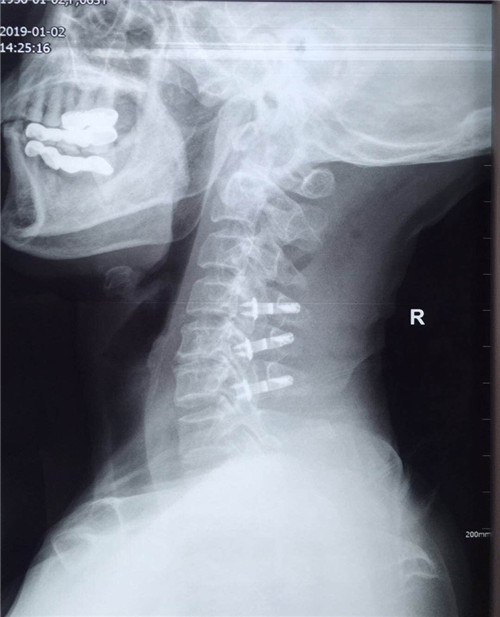

术前

患者入院后,骨一科医护人员为其做进一步检查,诊断为多发颈椎间盘突出并继发颈椎管狭窄症。经讨论研究后,程福宏副主任医师决定为其行颈后路颈4、5、6的单开门椎板扩大成形术,该手术在王小峰主治医师的配合下完成。术中,医生为患者进行彻底的减压脊髓,固定椎板。术后患者恢复较好,症状改善明显,已能够独自行走,恢复正常活动。